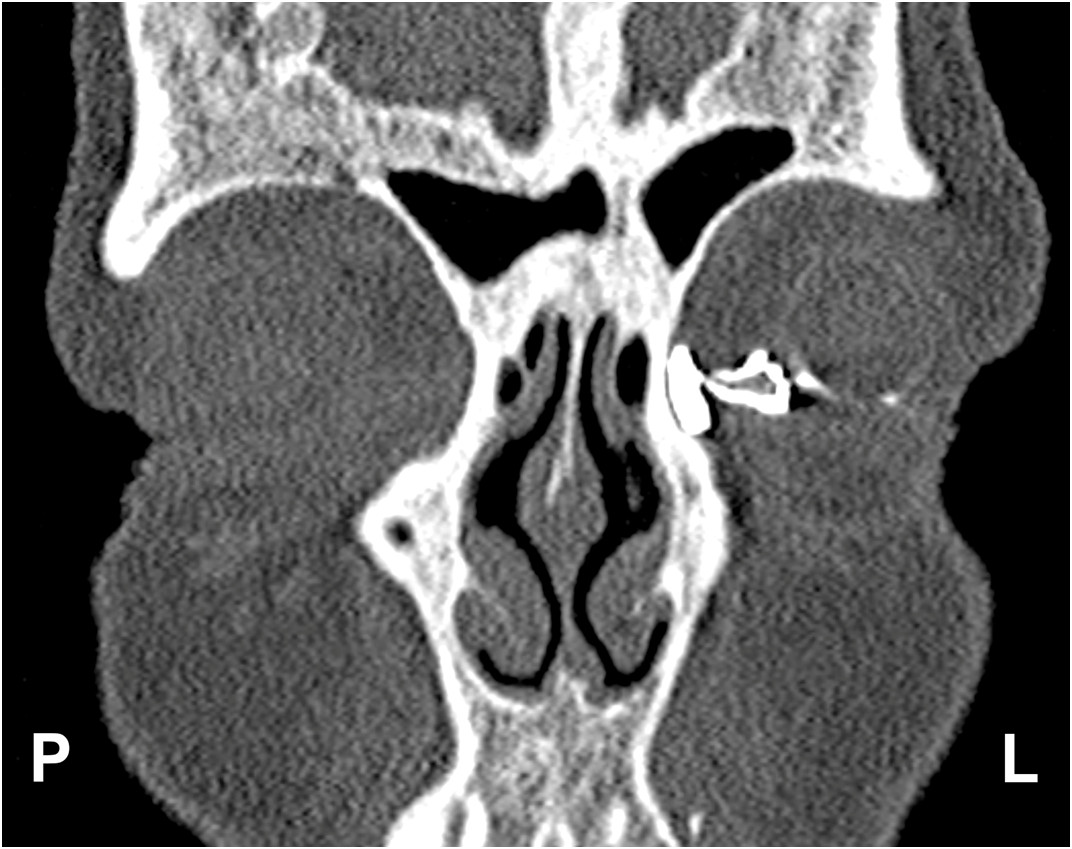

Rycina przedstawia obraz badania: